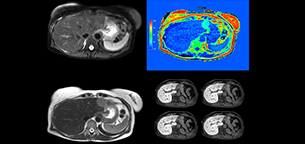

Dr. Kukuk’s liver exam begins with T2-weighted imaging, single shot and with fat suppression. “We always perform diffusion weighted imaging (DWI) with four b-values (0, 50, 250, 800) for lesion characterization, for monitoring after therapies, and for visualization of small lesions. Before giving contrast we routinely use the mDIXON Quant fat quantification sequence. Then we use dynamic e-THRIVE with an in-plane spatial resolution of 1.5 mm and high temporal resolution in just four breathholds of 13.1 seconds.” “Contrast enhancement is important to help us characterize lesions, for follow up in oncology patients and to inform clinicians when deciding on possible changes in the therapeutic regimen,” Dr. Kukuk explains. “Because we use liver-specific contrast agents we can obtain the T2-weighted images after the dynamic, to bridge the waiting time needed with these contrast agents. Just before the patient leaves the scanner we acquire another e-THRIVE in the axial plane and one or two coronals.”

Dr. Kukuk scans an increasing number of liver patients in an arms-up position using the integrated Posterior coil and a special positioning device. “By placing the patient’s arms up, the field of view in the right-left direction can be smaller so that a right-left preparation direction can be used to cut down the scan time,” he explains. “We can use high dS SENSE factors for TSE imaging, so we can shorten the echo train length. This results in a faster scan than arms-down T2 TSE and the images show high anatomical detail.”

“For DWI, the high dS SENSE factor allows using a shorter TE so we get higher signal and fewer susceptibility artifacts, which means less distortion of diffusion weighted images. Of course, with higher dS SENSE factors and the shortening of the TSE factor in T2-weighted imaging, we can drastically cut down the complete examination time. So, with arms-up we get faster images, less distortion in DWI and less blurring on T2-weighted images. Almost all patients tolerate the arms-up scanning well.”

“The mDIXON Quant fat fraction maps provide quantitative information and also anatomical detail. The sequence is fast, usually taking about 16 seconds, which is just a breath hold for most patients. It definitely improves our efficiency.”